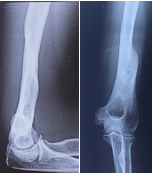

Case-IV

39 years, female;

Comminuted fracture distal humerus (Figure 14-17).

Figure 14 Post-operative x-ray after Ilizarov operation.

Figure 15 Picture with Ilizarov frame.

Figure 16 X-ray after union.

Figure 17 Picture after union.